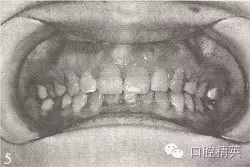

参见图9-33 双侧后牙锁颌矫治前后

B.双侧后牙锁颌矫治后